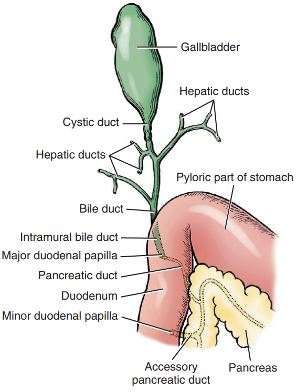

담낭은 간에서 만들어진 담즙을 저장하고, 소화 과정에서 필요한 담즙을 배출하는 기관입니다.

질환이 진행되어 담낭이 과도하게 팽창하면, 담낭벽으로 가는 혈류가 줄어들어 담낭 괴사가 일어나거나 이차적인 세균 감염 및 담즙 배출 장애를 유발합니다. 이는 결국 전신 상태를 급격히 악화시키며 생명을 위협하는 응급 상황으로 이어질 수 있습니다.

담낭에 염증과 괴사가 진행되면 결국 담낭 파열 이라는 최악의 상황에 이를 수 있습니다. 이때 유출된 담즙은 복강 내로 퍼져 복막염이나 췌장염 같은 심각한 전신 장기 손상을 일으킵니다. 이는 아이의 생명을 즉각적으로 위협하는 응급 상황이기에, 골든타임을 놓치지 않는 긴급 수술이 무엇보다 중요합니다.

설령 파열까지 진행되지 않더라도 안심할 수는 없습니다. 끈적하게 변한 점액질이 담관을 막아버리면 간에서 생성된 담즙이 배출되지 못해 심각한 전신 황달과 급성 간부전으로 이어질 수 있습니다.

초음파 검사상 단순 슬러지 단계를 넘어 점액종(Mucocele)으로 진행되었다면, 담낭 파열의 위험이 급격히 높아지므로 수술적 교정을 고려해야 합니다.

- 복부 초음파: 담낭 내부에 유동성이 없는 다량의 점액종(슬러지)이 확인되었으며, 특히 담낭 외측벽의 구조적 이상, 담관 확장, 췌장의 부종, 담낭 주위의 복막염 등 담낭 파열을 시사하는 강력한 소견들이 관찰되었습니다.

수술 중 확인한 담낭은 이미 파열되어 끈적한 담즙과 점액이 복강 내로 누출된 상태였습니다. 이로 인해 심한 복막염이 발생했을 뿐만 아니라, 담낭이 주변 장기들과 딱딱하게 달라붙는 유착 현상이 관찰되었습니다. 특히 총담관 주변까지 염증이 번져 주변 조직과 심하게 엉켜 있어 매우 정교한 수술이 필요한 상황이었습니다.

주변 장기와의 심한 유착으로 인해 수술의 난이도가 높았으나, 다른 장기에 손상이 가지 않도록 유착된 조직을 세밀하게 박리하여 분리해냈습니다. 이후 담관의 상태를 정밀하게 재확인하고, 의료용 헤모클립을 이용해 담관을 안전하게 결찰 한 뒤 문제가 된 담낭을 성공적으로 절제하였습니다.